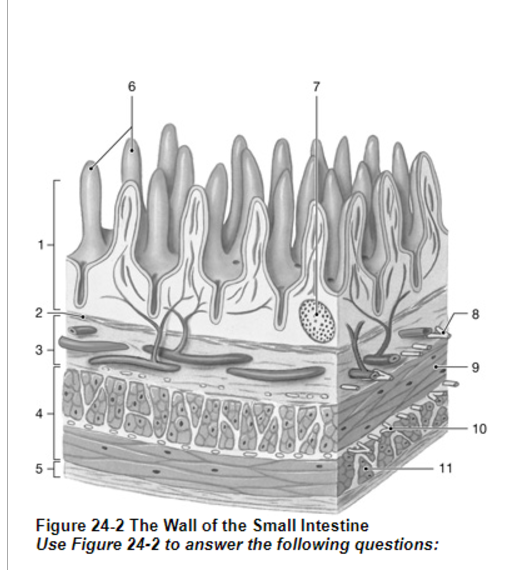

What is the layer labeled “4”?

Muscularis externa

What is the layer labeled “2”?

Muscularis mucosae

What is the layer labeled “3”?

submucosa

Which structure controls the contraction of the muscularis externa?

10